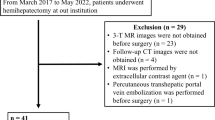

In this prospective trial we included patients who were scheduled for interventional PVE before extended hemihepatectomy. Patients with prior systemic chemotherapy or other therapies affecting the liver (surgical resection, transarterial chemoembolization, radiofrequency ablation, brachytherapy, radioembolization therapy) were excluded from the study.

Between January 2012 and December 2014, 37 patients (22 male, 15 female) with a mean age of 62.3 years (SD: 10.8) met the inclusion criteria. Twenty-four patients had cholangiocarcinoma, 11 had liver metastasis from colorectal cancer and one each had hepatocellular carcinoma (HCC) and large focal nodular hyperplasia (FNH). Total serum bilirubin at the time of PVE was 1.18 ± 1.41 mg/dl (range 0.3–7.4; normal value <1.2 mg/dl). Eight patients had elevated serum bilirubin (between 2.9 and 7.4 mg/dl) because of obstructive jaundice. All patients with cholangiocarcinoma and significant cholestasis in the left liver lobe (n = 13) received endoscopic stent placement to the left main duct before PVE. No patient had clinical or radiological signs of cirrhosis or renal impairment defined by a creatinine clearance lower than 50 ml/min Fig. 2 (Table 1).

A total of 131 MRI examinations were analysed. One patient did not undergo 14-days-post-PVE but 28-days-post-PVE MRI, six patients did not undergo 28-days-post-PVE MRI, and ten patients did not undergo 10-days-post-surgery MRI. Overall, 22 patients were examined at all four time points. Of the 37 patients, six patients did not receive extended hemihepatectomy because of extrahepatic disease which was revealed during laparoscopy. Four patients were not able to undergo post-surgery MRI because they were still in the intensive care unit.